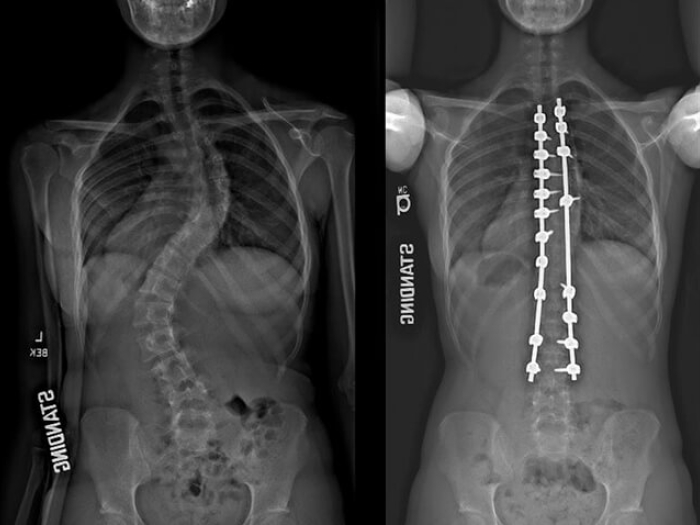

Xray image comparison of spine.

Health Lab

Drug combination reduces narcotic use, manages pain after surgery for teens with scoliosis

Narcotics after surgery often lead to side effects such as nausea, vomiting and itching.

For kids with severe scoliosis, growth-friendly surgeries cause more complications than single spinal fusion

The results of this study will allow parents of young children to make more informed decisions about treatment plans.